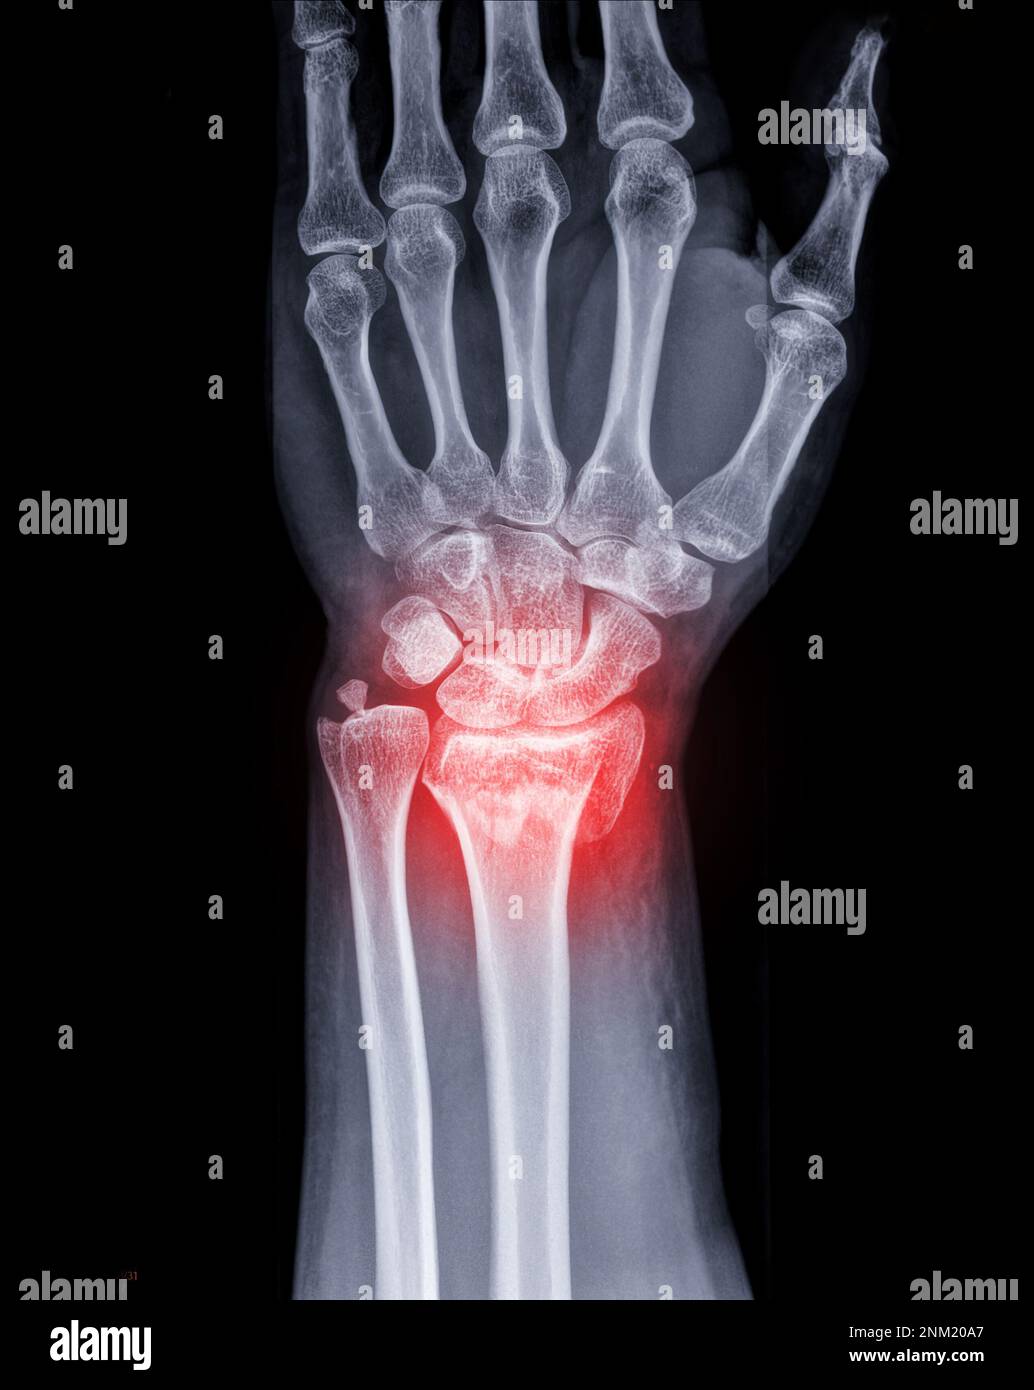

Fracture Du Poignet Gauche . les fractures du poignet localisées à l’extrémité inférieure du radius chez l’adulte sont très fréquentes. la fracture du poignet est généralement due à une chute sur une main tendue: cet article fait partie du dossier : Fracture du poignet chez l’adulte. les fractures du poignet sont généralement dues à une chute sur une main tendue. Quelles sont les principales causes des fractures du poignet ? Le radius se casse alors près du poignet, et l’extrémité cassée du radius est déplacée vers le Ces fractures peuvent généralement être identifiées sur des radiographies, mais une tomodensitométrie est parfois nécessaire. Combien de temps garder le plâtre ? c'est surtout l'extrémité du radius ou du scaphoïde qui se casse en cas de fracture au poignet. La plupart des fractures du poignet. Le poignet ne supporte pas le poids du corps et se brise. Il existe 2 types de traitement : douleurs et gonflement du poignet sont les symptômes les plus fréquents de la fracture du poignet. une fracture du poignet est une fracture de l’un des os de votre poignet.

Fracture Du Poignet Gauche Quelles sont les principales causes des fractures du poignet ? Combien de temps garder le plâtre ? Quelles sont les principales causes des fractures du poignet ? c'est surtout l'extrémité du radius ou du scaphoïde qui se casse en cas de fracture au poignet. une fracture du poignet est une fracture de l’un des os de votre poignet. cet article fait partie du dossier : La plupart des fractures du poignet. Ces fractures peuvent généralement être identifiées sur des radiographies, mais une tomodensitométrie est parfois nécessaire. douleurs et gonflement du poignet sont les symptômes les plus fréquents de la fracture du poignet. les fractures du poignet localisées à l’extrémité inférieure du radius chez l’adulte sont très fréquentes. Dans 50 % des cas,. la fracture du poignet est généralement due à une chute sur une main tendue: Le radius se casse alors près du poignet, et l’extrémité cassée du radius est déplacée vers le Le poignet ne supporte pas le poids du corps et se brise. Il existe 2 types de traitement : les fractures du poignet sont généralement dues à une chute sur une main tendue.

Image radiographique de l'articulation du gauche AP et vue Fracture Du Poignet Gauche La plupart des fractures du poignet. Fracture du poignet chez l’adulte. les fractures du poignet localisées à l’extrémité inférieure du radius chez l’adulte sont très fréquentes. les fractures du poignet sont généralement dues à une chute sur une main tendue. Combien de temps garder le plâtre ? Le poignet ne supporte pas le poids du corps et se. Fracture Du Poignet Gauche.